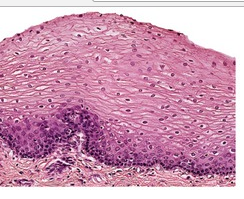

1. Stratified squamous

1. Function → protection, secretion, absorption, excretion Location → covers body surface, covers and lines internal organs, compose glands Characteristics → lack blood vessels, cells readily divide, cells are tightly packed together.

1. TYPES OF EPITHELIAL CELLS